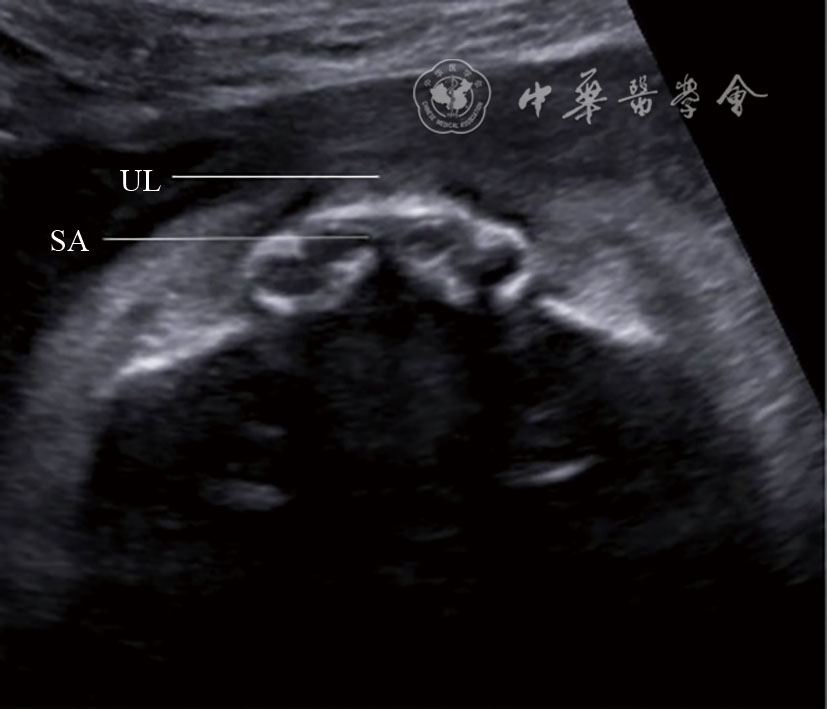

图15 上牙槽突横切面超声图像 注:UL为上唇;SA为上牙槽